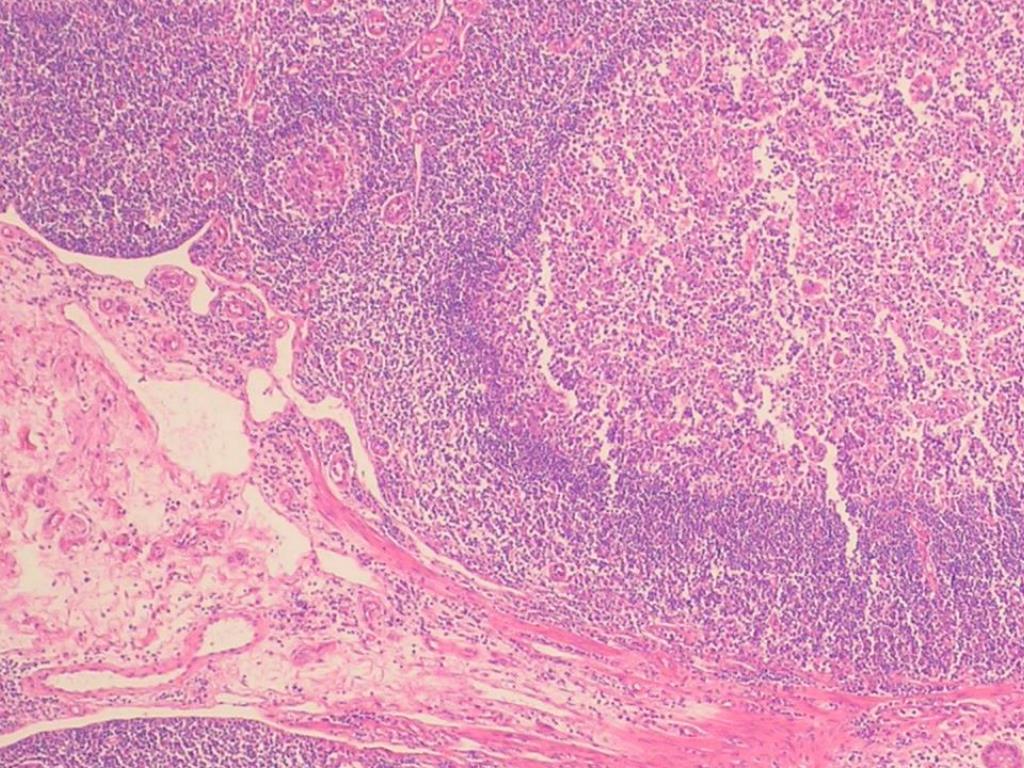

36. PATOLOGIA 外科医

41. PRODUCTO DE RESECCION INTESTINAL: APENDICITIS AGUDA FIBRINOPURULENTA, FIBROSIS PERIAPENDICULAR SEVERA. ILEON TERMINAL Y COLON CON HIPERPLASIA LINFOIDE FOLICULAR Y PERITONITIS AGUDA 外科医